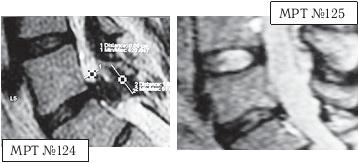

На МРТ № 124 состояние поясничного отдела позвоночника (до применения метода вертеброревитологии): в сегменте LIV-LV наблюдается выраженный дегенеративный процесс в межпозвонковом диске с разрушением пульпозного ядра, снижением его высоты; в сегменте LV-SI наблюдается секвестрированная грыжа межпозвонкового диска с разрывом задней продольной связки, абсолютный стеноз спинномозгового канала.

На МРТ № 125 того же пациента отмечается состояние поясничного отдела позвоночника после двух курсов лечения методом вертеброревитологии: в сегменте LV-SI наблюдается отсутствие грыжи межпозвонкового диска, спондилёз, небольшой участок гипертрофии задней продольной связки (в месте разрыва). Но самое примечательное то, что особо интересует вышеуказанных профессиональных специалистов, — в межпозвонковых дисках отмечен активный процесс репаративной регенерации. А в межпозвонковом диске в сегменте LIV-LV он практически достиг полной реституции!

сегмент LIV-LV (до лечения) сегмент LIV-LV (после лечения)

Примечание: как правило, на качественных снимках МРТ, очень чётко просматривается состояние диска, благодаря цветовой гамме. Тёмные участки межпозвонкового диска соответствуют участкам расположения некротизированных тканей (мёртвых клеток). Светлые участки межпозвонкового диска соответствуют участкам расположения функциональных тканей (живых клеток).